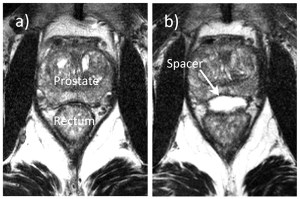

The placement of the SpaceOAR hydrogel is a bit more complicated. The material is similar to the dermal fillers used by aesthetic cosmetic surgeons to fill in depressions or wrinkles in facial features. It is biodegradable so the original volume is absorbed by the body over a period of 6 -9 months. SpaceOAR was recently approved by the FDA (April 2015) for use in urological radiation oncology. The material is injected between the rectal wall and the prostate to widen the separation between those two tissue areas, significantly reducing the possibility of radiation injury to rectal tissue during stereotactic body radiation therapy (SBRT). The following images are from a clinical showing a MRI scan of the prostate area before (a) and after (b) in the placement of the SpaceOAR hydrogel.